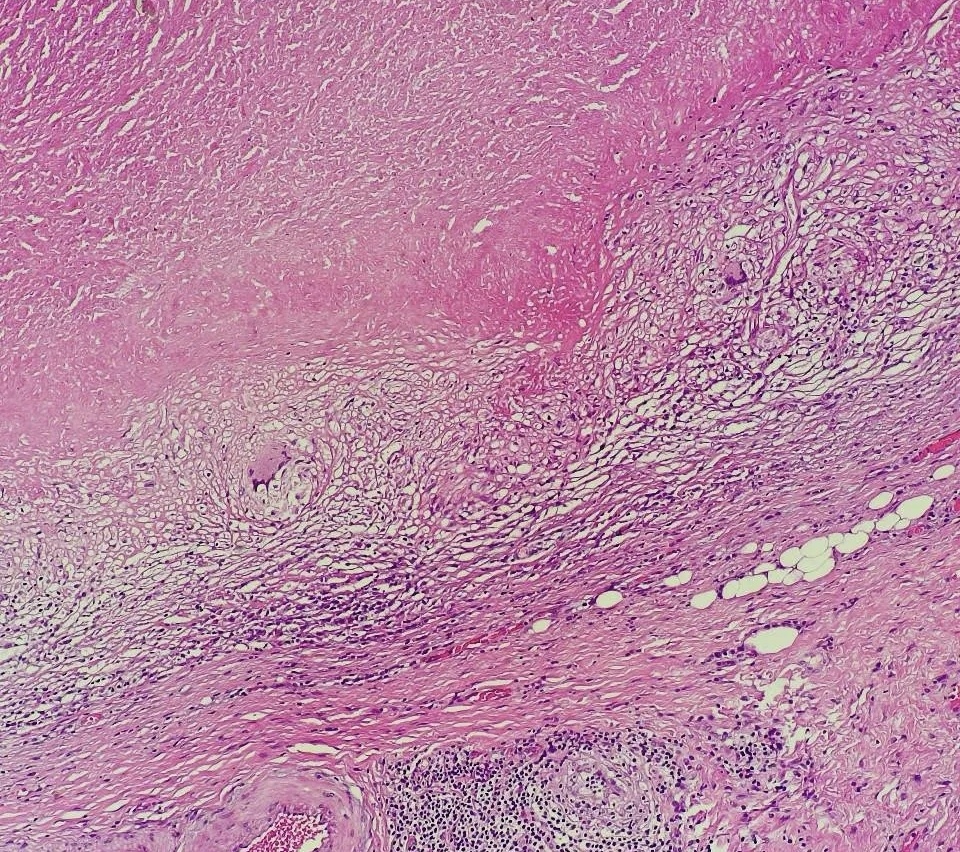

图①:淋巴结结核 图②:淋巴瘤 图③:箭头所指转移癌